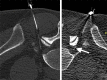

Spinal injection procedures can be performed blindly or, more accurately, with fluoroscopic or computed tomography (CT) guidance. Radiographic guidance for selective nerve root blocks and epidural injections allows an accurate needle placement, reduces the procedure time and is more secure for the patient, especially in patients with marked degenerative changes and scoliosis, resulting in a narrowing of the interlaminar space. Limiting factors remain the availability of scanners and the radiation dose. Interventional CT scan protocols in axial CT-acquisition mode for epidural and periradicular injections help to limit the radiation dose without a significant decrease of image quality. The purpose of this retrospective study was to analyze the effective radiation dosage patients are exposed during CT-guided epidural lumbar and periradicular injections. A total amount of n=1870 datasets from 18 months were analyzed after multiplying the dose length product with conversion factor k for each lumbar segment. For lumbar epidural injections (n=1286), a mean effective dose of 1.34 mSv (CI 95%, 1.30-1.38), for periradicular injections (n=584) a mean effective dose of 1.38 mSv (CI 95%, 1.32-1.44) were calculated.